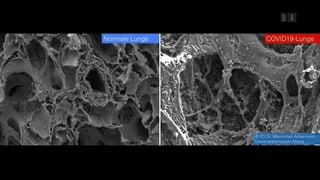

Simulation Zeigt Ausmass Was Covid 19 In Der Lunge Anrichtet Mz De

Coronavirus Video Zeigt Was Covid 19 In Der Lunge Anrichtet

Welche Sichtbaren Schaden Covid 19 In Der Lunge Anrichtet Video

www.t-online.de

Coronavirus Was Covid 19 In Der Lunge Anrichtet Der Spiegel